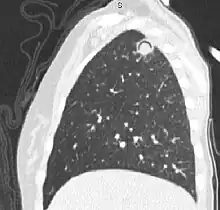

| The arrows denote an ill-defined nodular opacity in medial aspect of right upper lobe with ill-defined rim of lucency surrounding it | |

Sagittal reformat from a CT scan of the chest showing air crescent sign in a patient with invasive fungal infection. There is a rounded cavity in the apical right upper lobe, with a non-dependant soft-tissue nodule within it. Also there is some subtle ground-glass opacity surrounding the lesion.